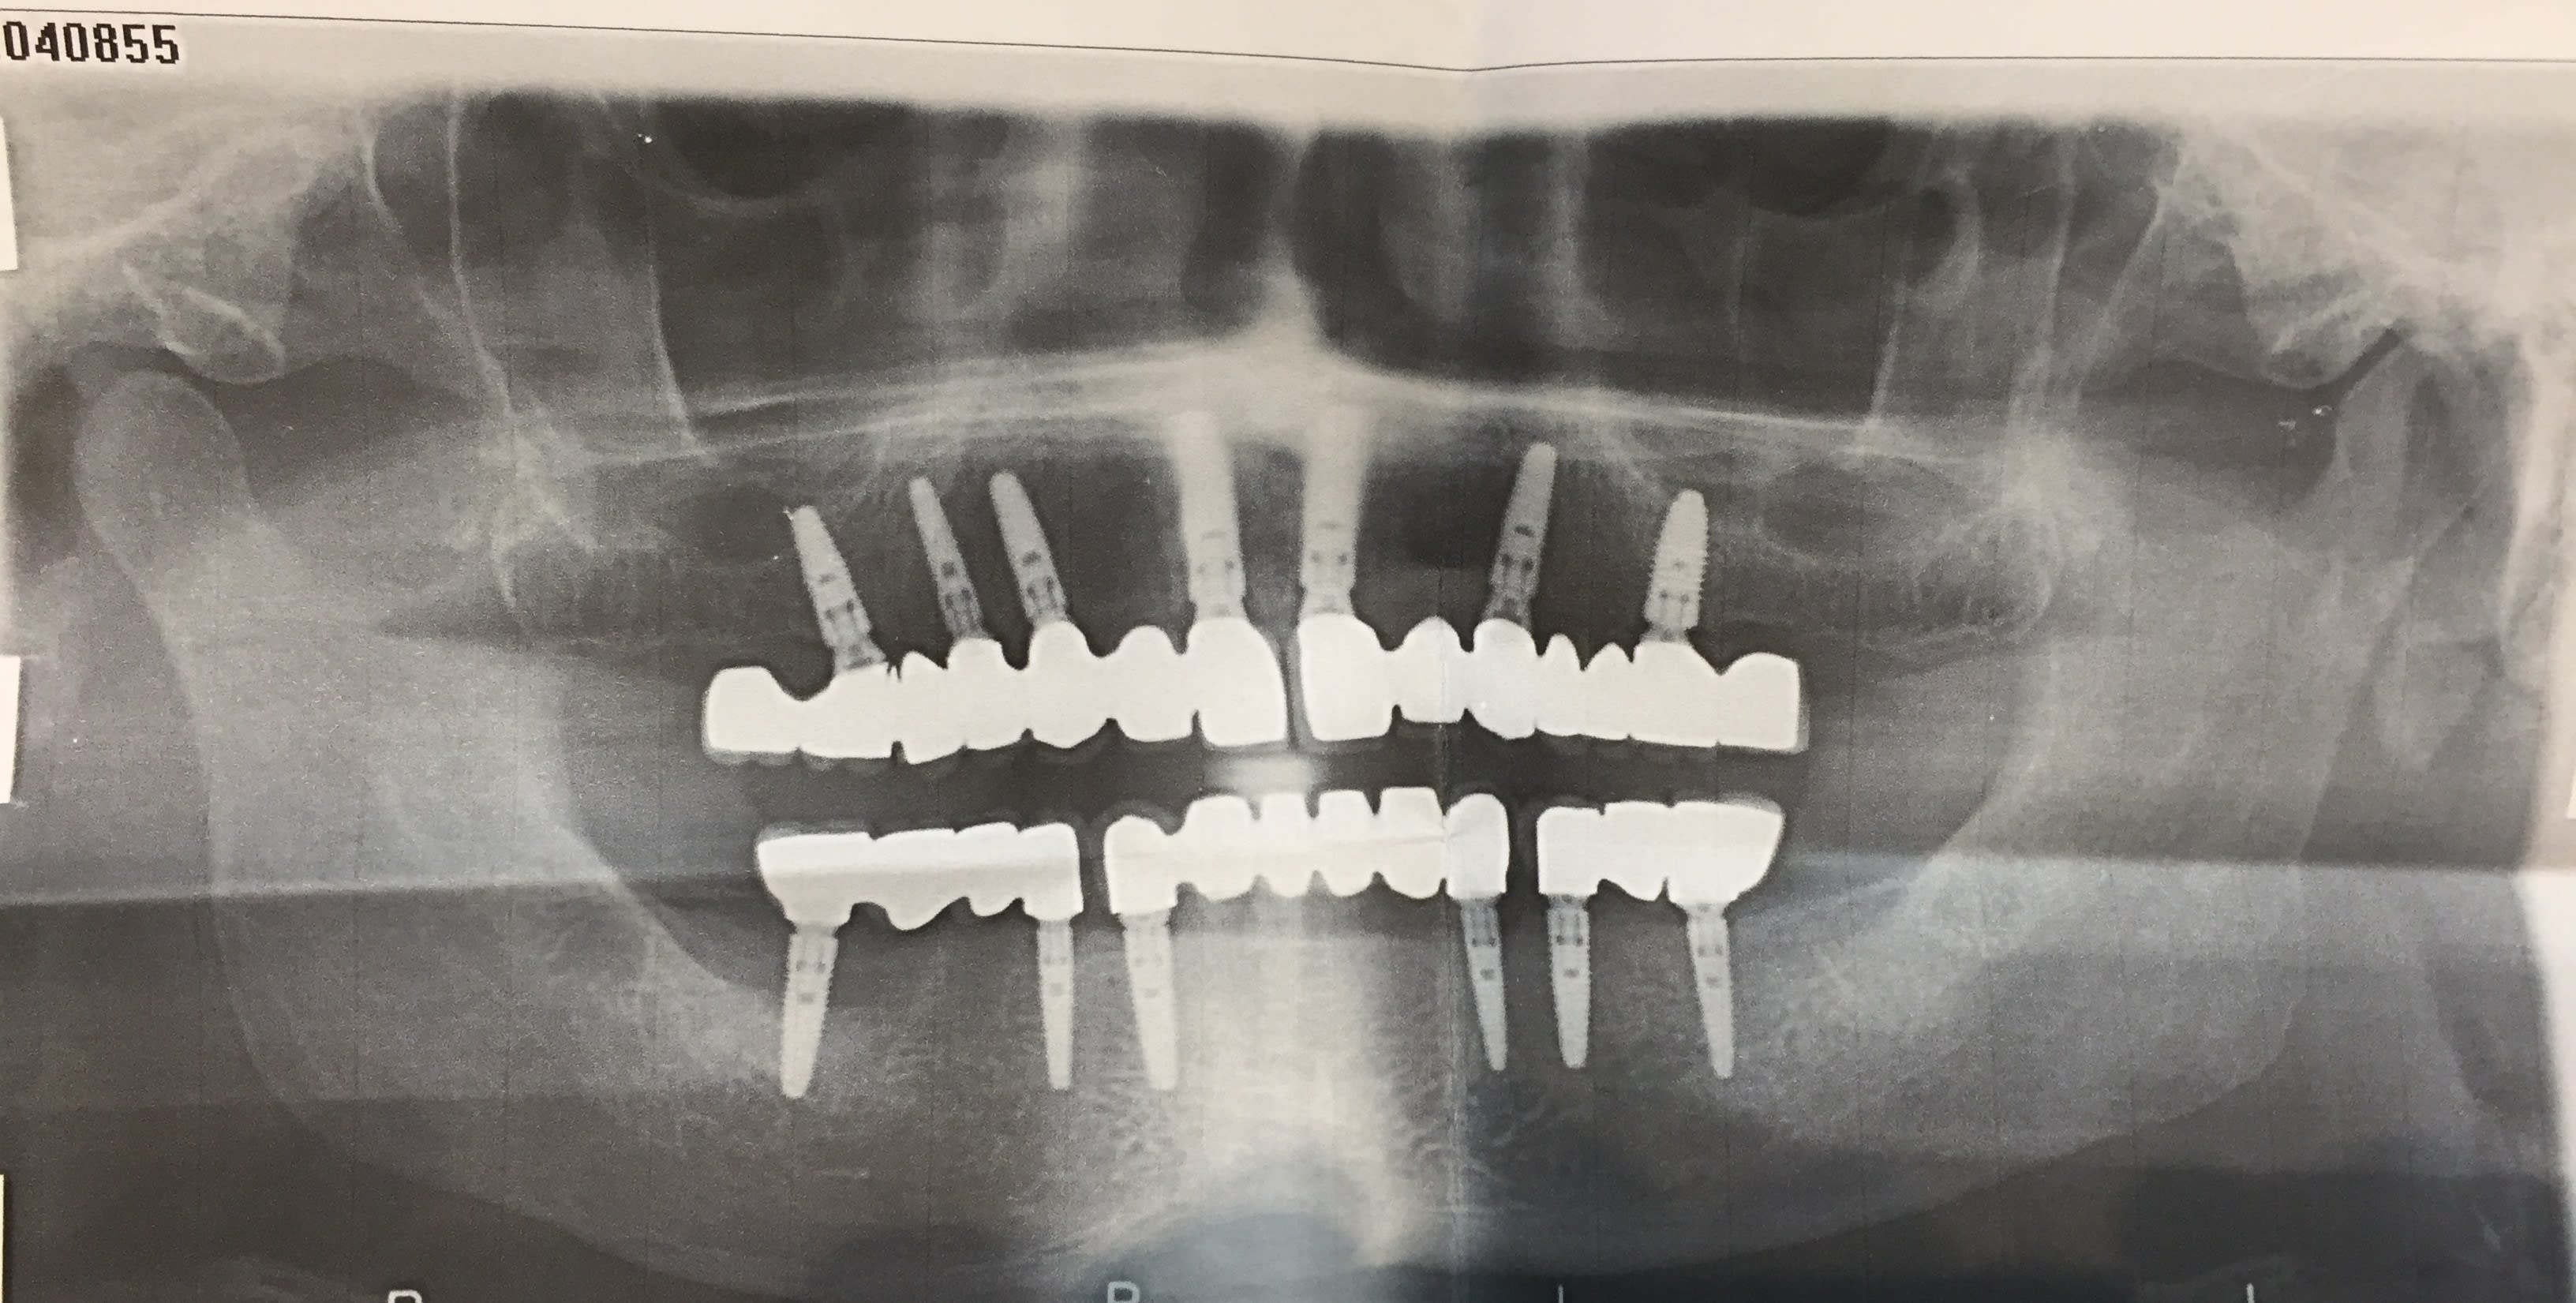

Un patient qui a réaliser les travaux en hongrie, opt en PJ

Le patient était deja venu le 2/8/16 pour resceller le bridge secteur 2 (pilier 26 devisser)

Il revient aujourd'hui pour le bridge secteur 1 qui s'est fracturé (fracture entre 15-16). J'ai déposé les élements 16-17.

Le patient me dit que les implants sont du Nobel

et puis tu lui suggères aussi de s'occuper de la périimplantite de l'implant en 47...;-)

m'est d'avis que c'est lié à la fracture du bridge sup...(sur-occlusion vraisemblable...)

Tu penses que c'est une PI ? On dirait que l'implant a été posé comme ça, y'a pas de cratérisation...

alors on voit pas la même chose...pour moi il y a cratérisation...(ou alors çà peut être aussi une ROG qui a merdé...)

reste que la moitié des spires exposées...çà va pas durer...